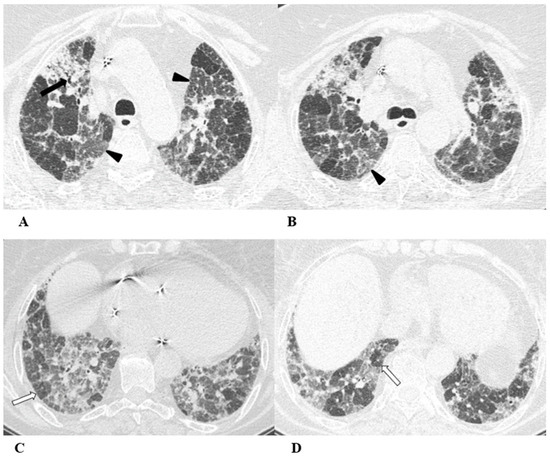

Figure 3.

Hypersensitivity pneumonia (HP). Hypersensitivity pneumonia is characterized by lymphocyte infiltrates that thicken the alveolar septa, with poorly formed non-necrotizing granulomas and multinucleated giant cells.

Typical HRCT features of acute HP are multiple bilateral small centrilobular nodules with upper lung zone predominance, lobular areas of decreased attenuation and vascularity suggestive of “air trapping” and patchy and/or diffuse GGO areas [9,12,17]. Chronic HP shows a typical “three density pattern” characterized by bilateral and diffuse lobular areas of decreased attenuation (air-trapping areas), patchy areas of real GGO in a predominant peribronchovascular distribution with traction bronchiectasis and bronchiolectasis inside (fibrosis signs), and also areas of a relative increase in density related to the normal CT appearance of the lung (GGO-like areas).

The ICI-associated HP pattern is indistinguishable from that of HP induced by allergen exposure. For this reason, in addition to the exclusion of atypical pneumonia, accurate exposure history is essential for the correct evaluation of the patient.

(A–D) A 76-year-old woman with colorectal cancer who received nivolumab and ipilimumab as second-line treatment. Seven months later, the patient presented worsening cough and dyspnea, along with weight loss, but she was able to undergo HRCT examination just two months after the onset of symptoms.

Axial chest CT scans of the upper lobes (A,B) show patchy GGO areas (black arrowheads) with over-imposed reticulation in a predominant peribronchovascular distribution and early traction bronchiectasis (black arrow).

Bilateral areas of decreased attenuation (air trapping) (white arrows) with geometric morphology are easily recognizable in both the inspiratory (A,B) and expiratory (C,D) acquisitions.